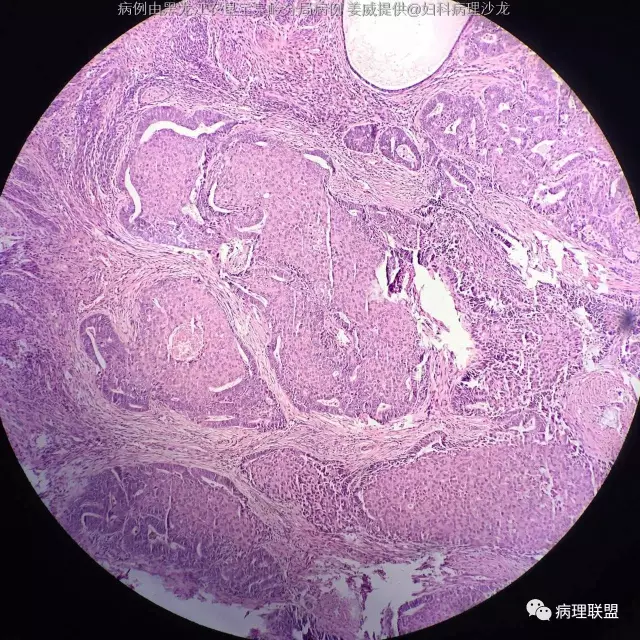

女 45岁,子宫内膜 全切子宫 术前非典(病例由黑龙江农垦宝泉岭分局病理 姜威提供,致谢!)

@黑龙江农垦宝泉岭分局病理 姜威 :子宫内膜样癌伴鳞状分化